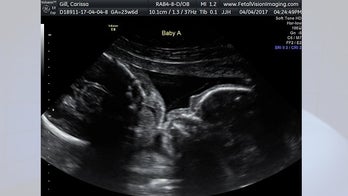

April 10, 2017 Ultrasound shows twins kissing in mother's womb Carissa Gill, a Croydon woman who is 24 weeks pregnant with twins, shared a special moment with her boyfriend on Tuesday while visiting Fetal Vision Imaging in Levittown.